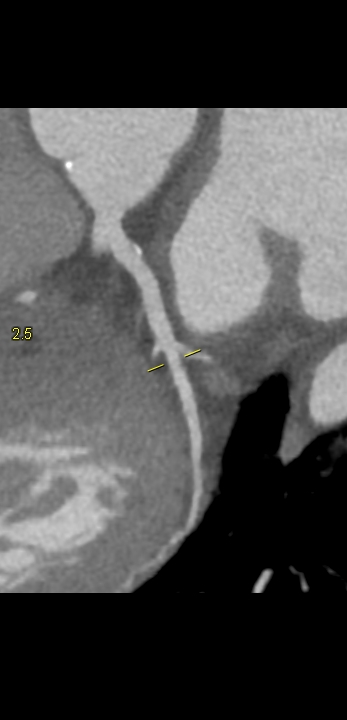

Figururile 1-9: reconstrucție în axul lung al vasului pentru arterele coronare cu evidențierea unui calibru global crescut la nivelul acestora și cu încărcătură ușoară-moderată de placă în principal calcificată

Discuţie caz nr 132: Examinările coroCT se efectuează în principal pentru aprecierea încărcăturii de placă precum și pentru evidențierea reducerilor de lumen ce necesită tratament. Această examinare a evidențiat creștere globală a calibrului arterelor coronare și o încărcătură ușoară-moderată cu placă în principal calcificată, fără a se evidenția arii de stenoză.

DE LUAT ACASĂ!!! Ectazia coronariană este o afecțiune rară caracterizată prin dilatarea anormală (diametrul vasului este de 1.5 ori mai mare) a arterelor coronare, care poate duce la afectarea fluxului sanguin și la un risc crescut de ischemie. Etiologia nu este cunoscută iar afecțiunea poate fi asociată cu ateroscleroză sau factori congenitali și reprezintă o provocare atât în diagnostic, cât și în tratament. Simptomele se suprapun adesea cu cele ale altor boli coronariene, ceea ce face ca identificarea timpurie să fie crucială. Opțiunile de tratament variază de la tratamentul medical cu terapie antiplachetară sau anticoagulantă până la proceduri intervenționale, cum ar fi angioplastia sau intervenția chirurgicală, în funcție de severitatea și riscul de complicații. Tratamentul pe termen lung se concentrează pe prevenirea evenimentelor ischemice și pe abordarea cauzelor care stau la baza acestora.